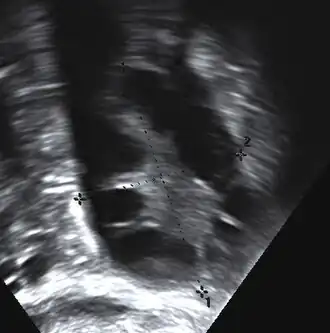

Gynecologic ultrasonography first looks for small ovarian follicles.[75] To count as polycystic ovaries, at least 20 follicles need to be present, smaller than 9 mm. This used to be 12 in older diagnostic criteria.[16] A less clear marker of PCOS is enlarged ovaries.[75] Ovary need to be at least 10 cm3 to count.[16] For sexually active individuals or those that agree, a transvaginal ultrasound approach is preferred. Alternatively, AMH levels can be tested in the blood.[75] Laparoscopic examination may reveal a thickened, smooth, pearl-white outer surface of the ovary. This would usually be an incidental finding if laparoscopy were performed for some other reason, as it would not be routine to examine the ovaries in this way to confirm a diagnosis of PCOS.[78]

-

Transvaginal ultrasound scan of polycystic ovary